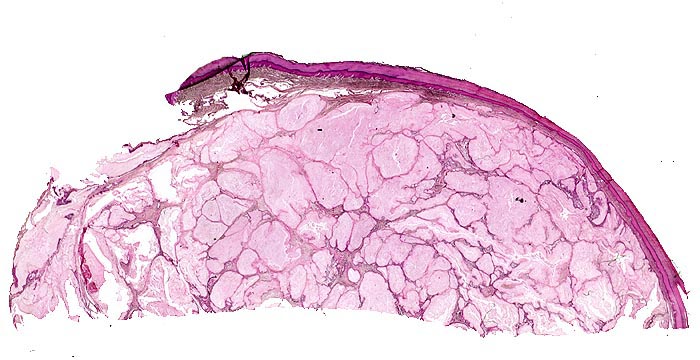

• Kollagenes Bindegewebe mit Tophus bestehend aus wolkiger eosinophiler Matrix mit herdförmig erkennbaren nadelförmigen Strukturen (Uratkristalle).

• Die Ablagerungen sind umgeben von mehrkernigen Fremdkörperriesenzellen, Makrophagen und wenigen neutrophilen Granulozyten.

Bei einer Gicht sind kristallin ausgefällte Natriumuratkristalle in den neutrophilen Granulozyten des Gelenkergusses und kalkweisse Auflagerungen am Gelenkknorpel nachweisbar. Kristallablagerungen in Form von Gichttophi mit einer granulomatösen Fremdkörperreaktion finden sich ausserhalb von Gelenken auch in Sehnenscheiden (Achillessehne), Weichteilen (Ohrläppchen, Ellenbogen, Knie), in der Achillessehne oder im Nierenparenchym. Die Löslichkeit von Harnsäure nimmt mit der Umgebungstemperatur ab, sodass die Kristallablagerungen vorwiegend peripher vorkommen. Am häufigsten betroffen ist das Grosszehengrundgelenk (Podagra), gefolgt von Sprunggelenk, Ellenbogengelenk, Kniegelenk und anderen Gelenken an Fuss und Hand.